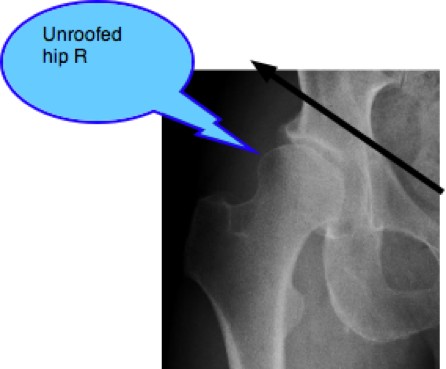

In the adult, the ball of the hip is partially unroofed; it juts out of the socket, giving reduced femoral head acetabular contact. The full weight of the body is thus distributed over a much smaller area of the hip and the result is progressive degenerative arthritic change. Unless action is taken timeously, the hip gradually changes from HYPERmobile TO HYPOmobile.

In the adult, the ball of the hip is partially unroofed; it juts out of the socket, giving reduced femoral head acetabular contact. The full weight of the body is thus distributed over a much smaller area and the result is progressive degenerative arthritic change.

Mr P's right hip: Hip Dysplasia

Note the sloping acetabulum, an unroofed one-third of the femoral head, the shallow socket and the beginnings of arthritis at the superior labral margin. Progressive hip arthritis.

Femoro acetabular impingement syndrome

Interestingly, there is also a suggestion of CAM deformity of the femoral head, contributing to the stiffness in the hip. FEMORO ACETABULAR IMPINGEMENT SYNDROME. Oddly, occasionally developmental hip dysplasia and FAIS can coexist in the same hip, producing confusing signs and symptoms.